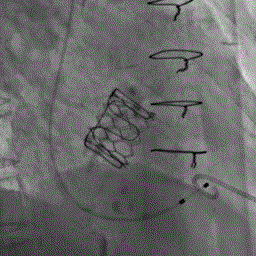

术前左室造影见大量反流 术后左室造影无反流

瓣中瓣释放